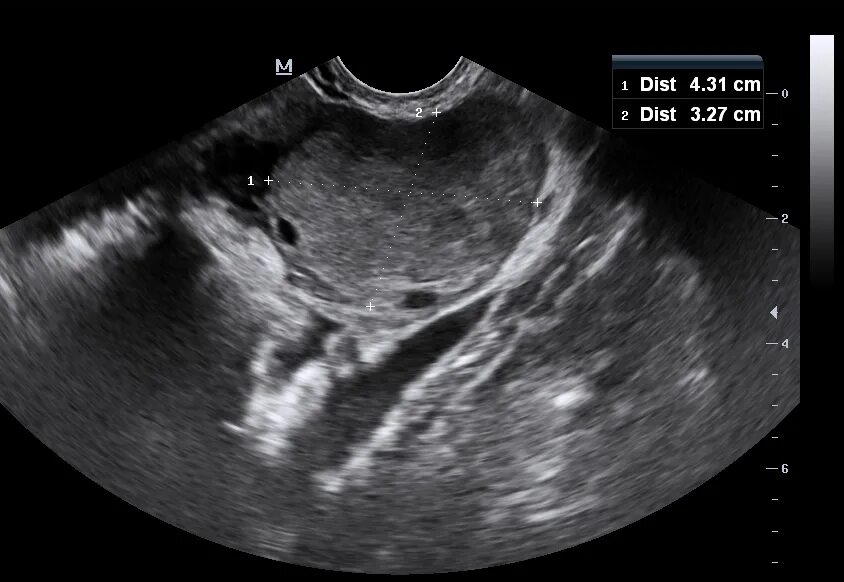

Метастазы в матке